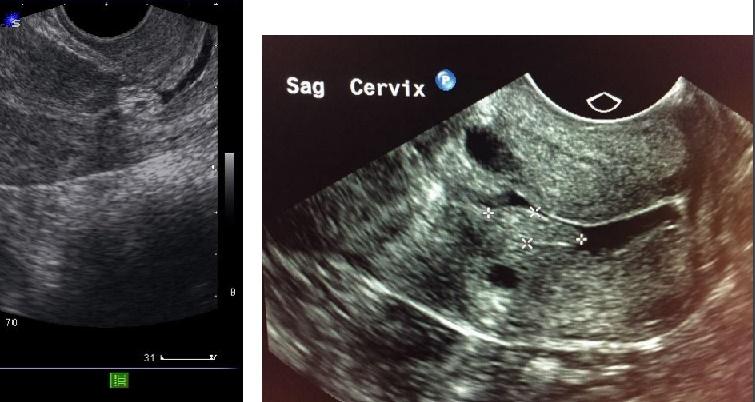

Enfermedades Cervix

Cervix (Cuello)

Nabothian Cyst

Quistes producto de retención de fluido en endocervix.

Anecocios, miden 3mm y llegar a 3cm.

Pólipos

- Sólidos, benignos, masas de tejido adheridas a la pared cervical

- Pequeños focos ecogénicos en la cervix

Nabothian Cyst (imagen)

Pólipo en Cervix (imagen)